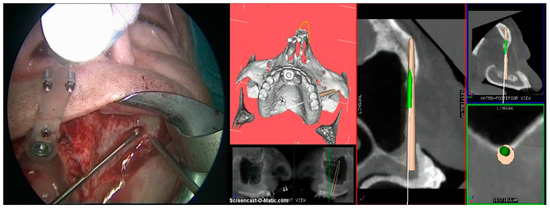

2. Case Report

3. Procedure

- Step 3. Image-to-patient registration via registration templates, external registration frames, or bone markers.

- Step 4. Surgery: navigation of the drill along the predefined surgical plan.